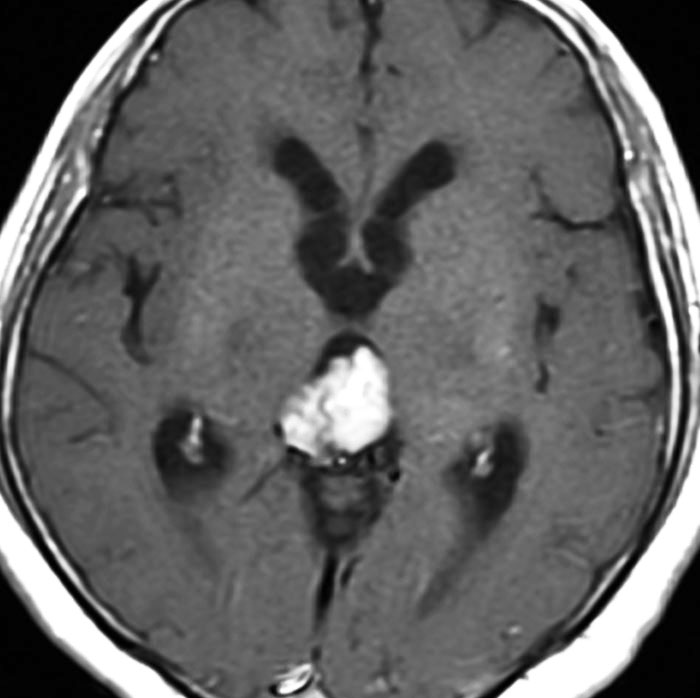

成人男性が早朝の頭痛で発症しました。閉塞性水頭症になっているので第3脳室開窓術が行なわれてから紹介されてきました。開頭手術で全摘出して,病理が PPTID グレード3でしたので,脳脊髄照射 24Gy/12fr と腫瘍局所照射 54Gy/27fr をしました。